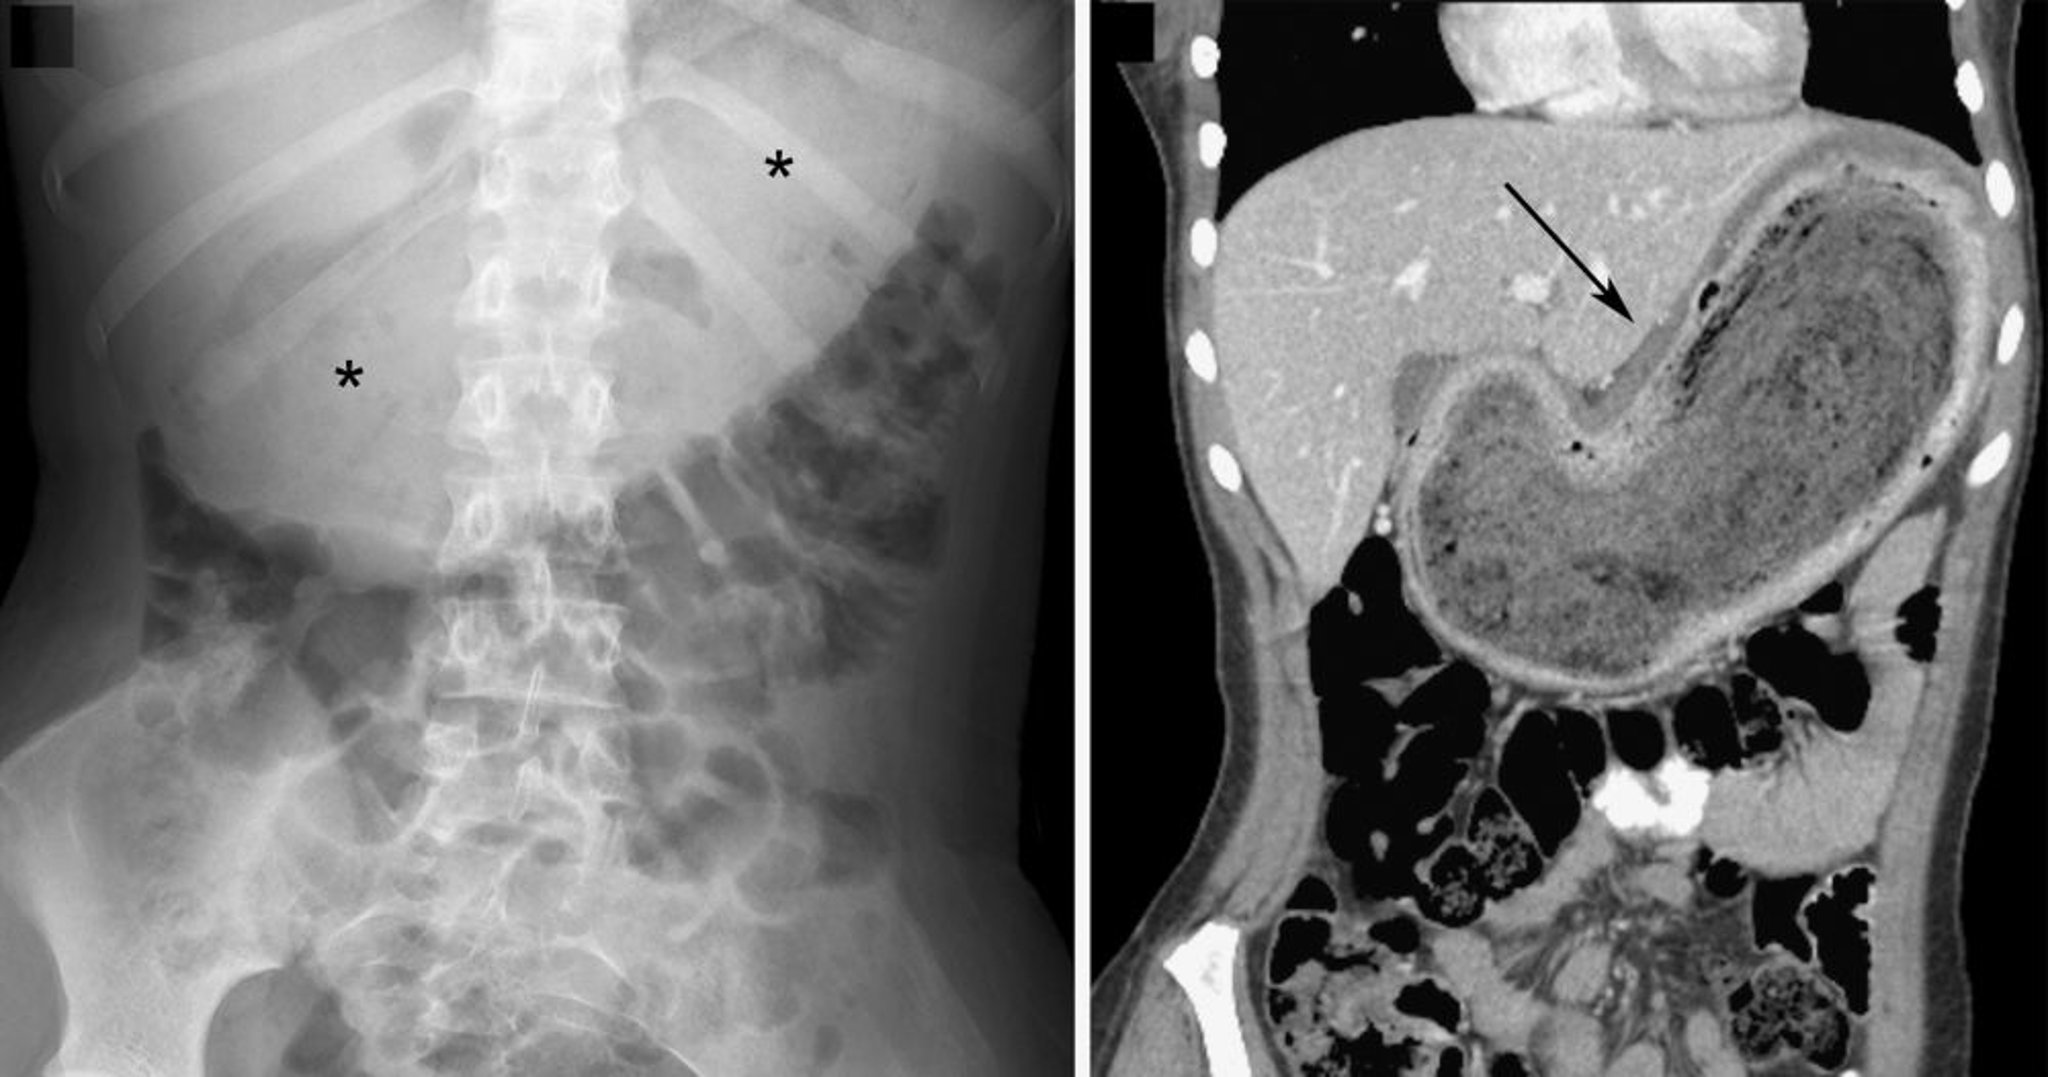

Bezoar (hallazgos en los estudios de diagnóstico por imágenes)

En la radiografía a la izquierda, el bezoar se indica por la gran masa de tejido blando en la línea media abdominal superior con un patrón moteado de gas intralesional (asteriscos). En la imagen coronal de TC a la derecha, el bezoar está indicado por la masa heterogénea (flecha). En ambas imágenes, hay un desplazamiento inferior de las asas intestinales.